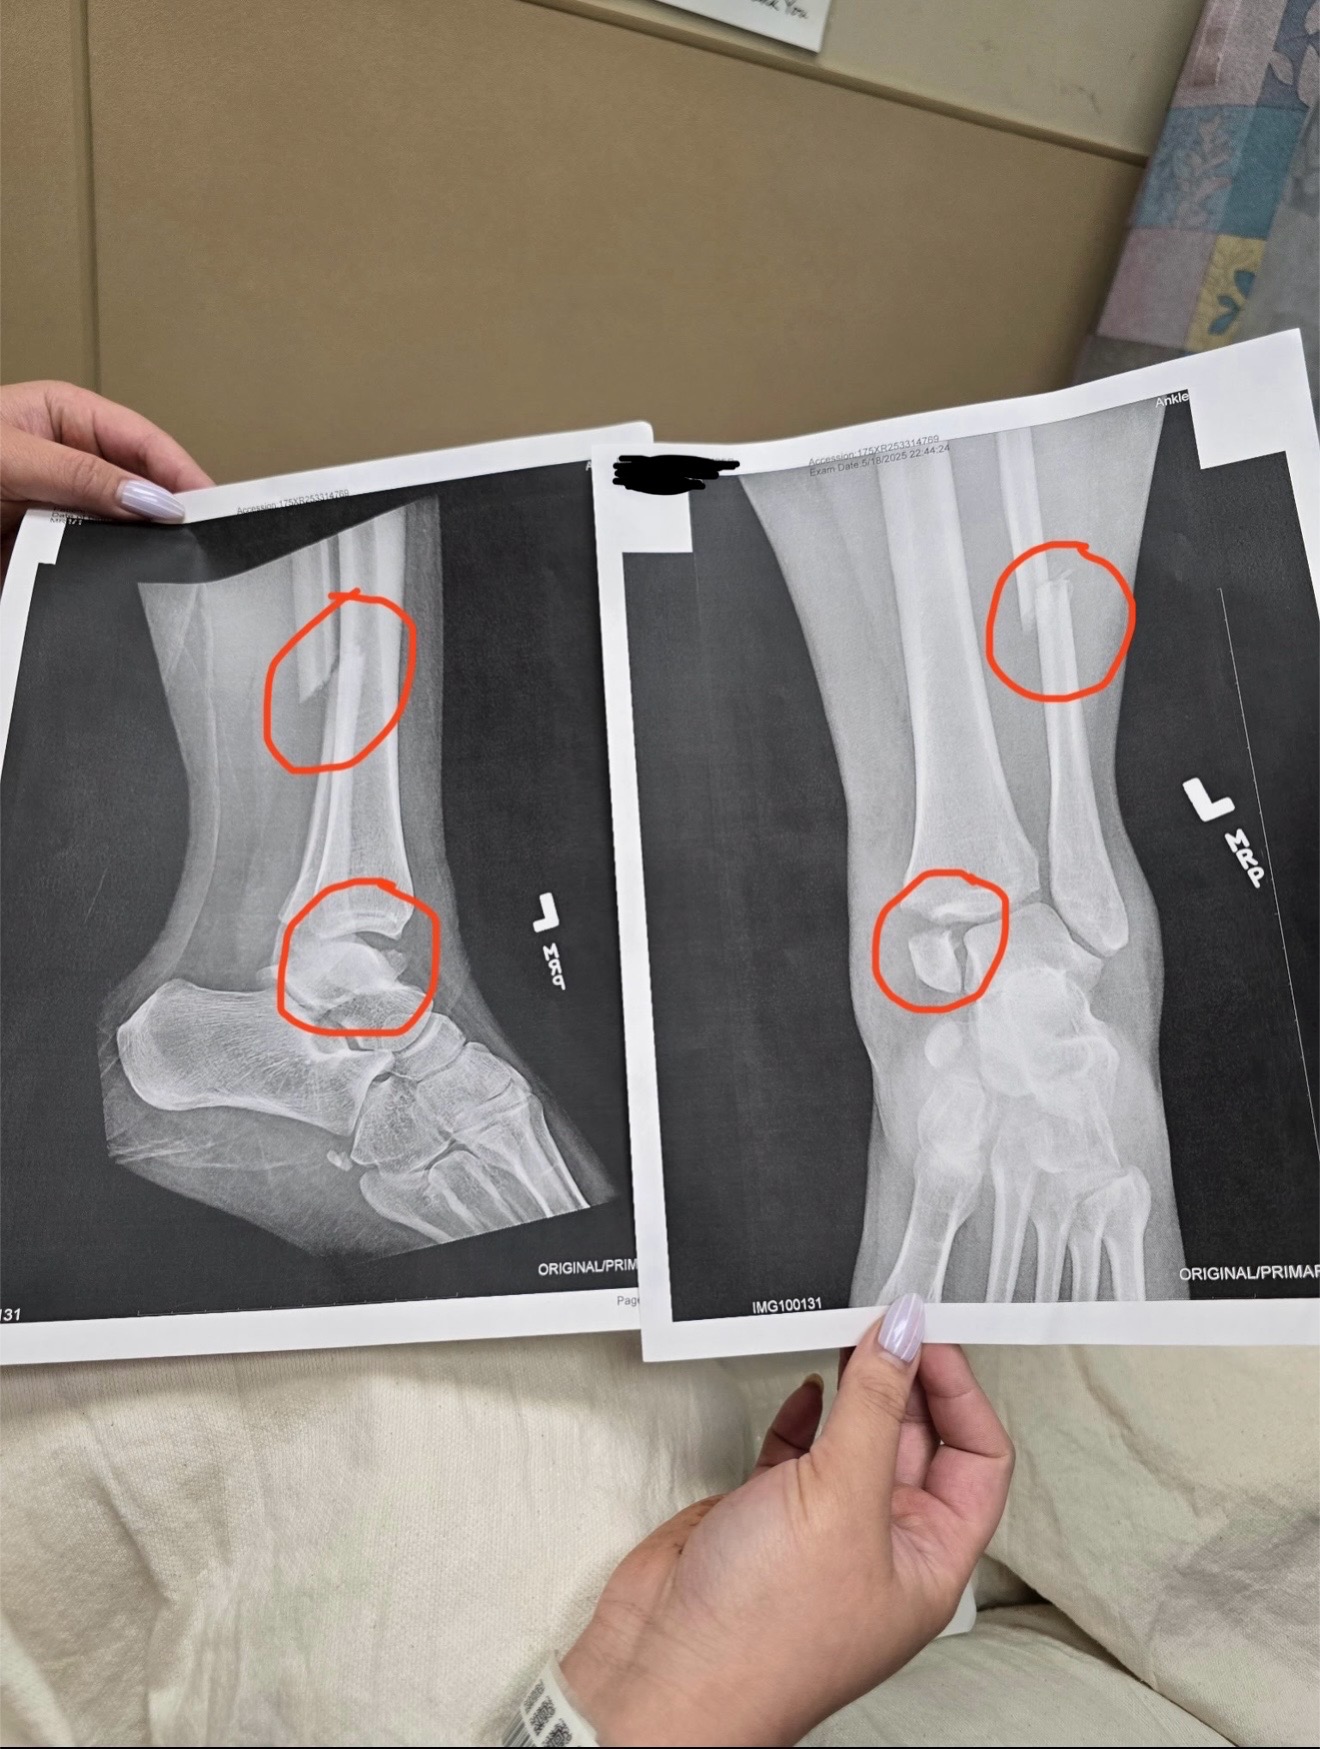

Hi I’m Amber and a week ago, I suffered a serious accident—I fell and broke both my leg and ankle. I was rushed to the ER, where X-rays revealed a torn ligament and multiple fractures in my tibia and fibula, with my tibia near the ankle essentially shattered. The injury is so severe that, even with surgery, it will never fully heal to what it once was.